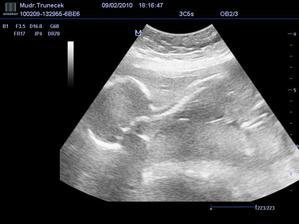

Náš František a jeho mladší sourozenec

Dne 17.10.2009 mamka zjistila, že, ač neplánovaně, budu mít sourozence.TP je zatím 21. 6.2010.